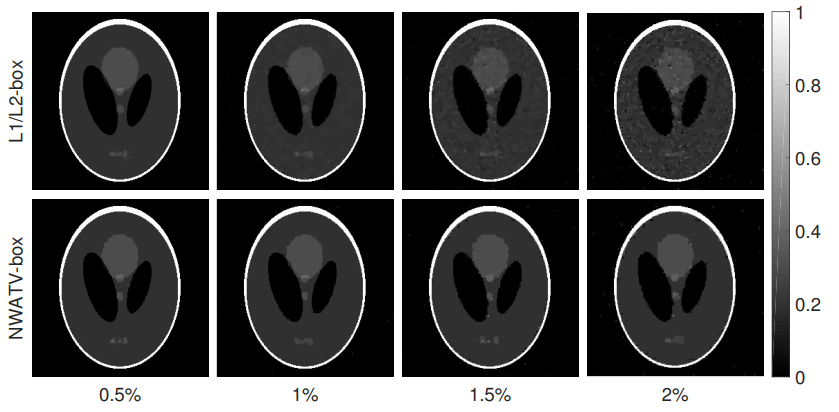

• Sparse-view computed tomography (CT) is an important way to reduce the negative effect of radiation exposure in medical imaging by skipping some X-ray projections. However, due to violating the Nyquist/Shannon sampling criterion, there are severe streaking artifacts in the reconstructed CT images that could mislead diagnosis. Noting the ill-posedness nature of the corresponding inverse problem in a sparse-view CT, minimizing an energy functional composed by an image fidelity term together with properly chosen regularization terms is widely used to reconstruct a medical meaningful attenuation image. In this paper, we propose a regularization, called the box-constrained nonlinear weighted anisotropic total variation (box-constrained NWATV), and minimize the regularization term accompanying the least square fitting using an alternative direction method of multipliers (ADMM) type method. The proposed method is validated through the Shepp-Logan phantom model, alongisde the actual walnut X-ray projections provided by Finnish Inverse Problems Society and the human lung images. The experimental results show that the reconstruction speed of the proposed method is significantly accelerated compared to the existing $ L_1/L_2 $ regularization method. Precisely, the central processing unit (CPU) time is reduced more than 8 times.